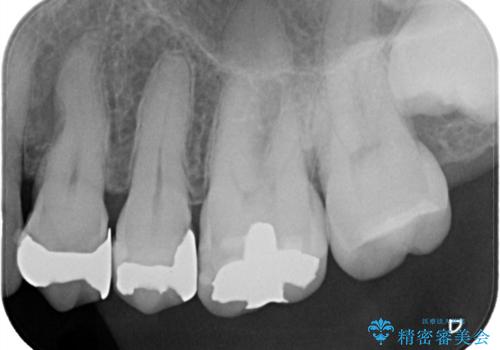

- 定期健診にて虫歯が見つかった患者さんです。県外からお越しいただいている事もあり、かなりお久しぶりの来院でした。歯と歯の間のところと銀歯の下が虫歯になっていました。被せ物はオールセラミッククラウンで治療しました。

銀歯を外すとかなり大きな虫歯になっていました。幸いぎりぎりのところで神経まで虫歯は広がっていなかったため、症状が出ない事を確認した後、オールセラミッククラウンで治療しました。虫歯除去後、残っている歯質が少なかったため、破折抵抗を考慮し部分的な被せ物ではなくクラウンを選択しました。

※被せ物では歯と被せ物の適合がとても大切になります。適合が悪い被せもの(歯と被せものの間に隙間がある)を入れるとそこに汚れが溜り虫歯の原因となります。当院では精度が高い被せものを追求するため、サージテル(拡大鏡)や型取りの材料にシリコン材を使用しています。